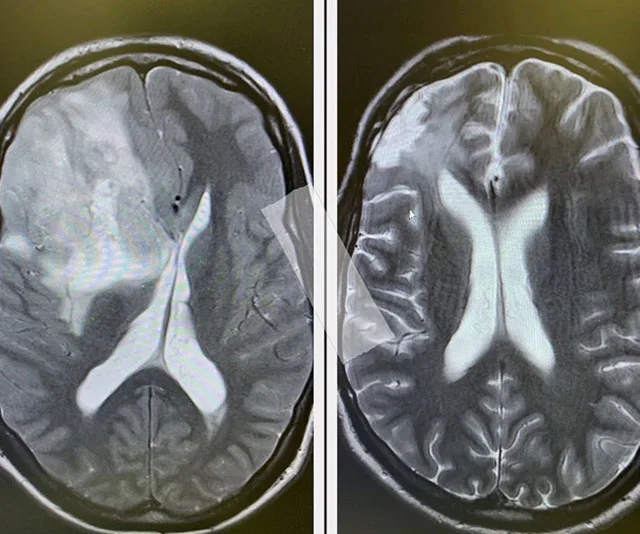

In August this year, Johnny shared two side-by-side brain scans, revealing he is cancer-free.

(Image: @johnny_ruffo/ Instagram)

Johnny was diagnosed with brain cancer in 2017 and had surgery to remove a tumour.